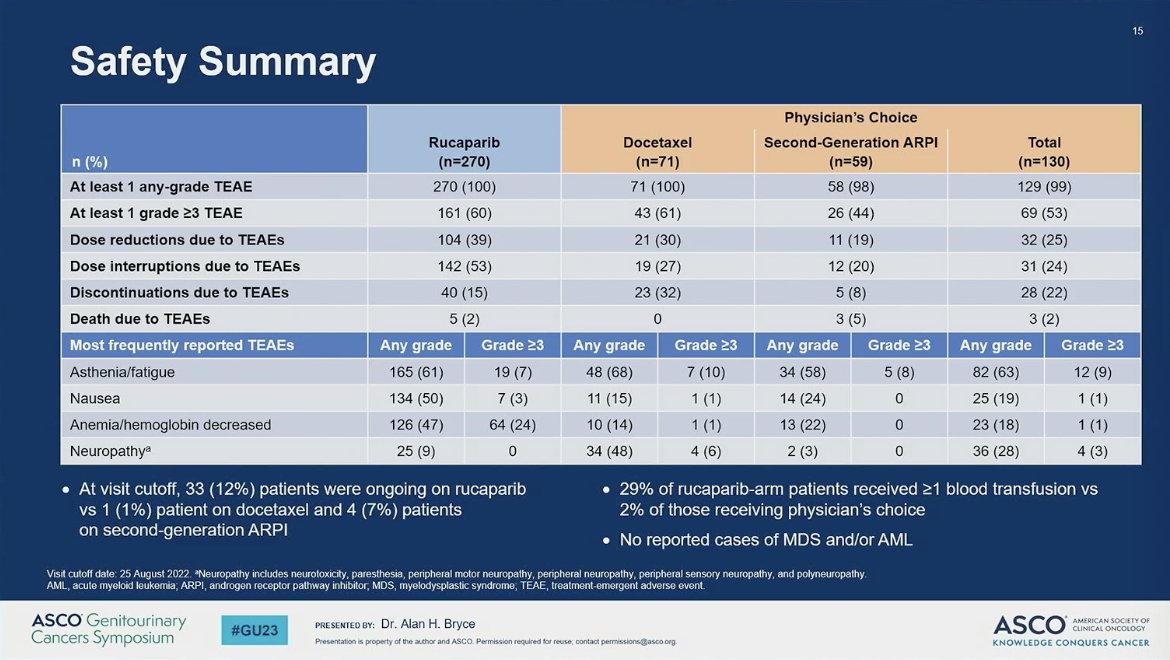

Rucaparib or Physician's Choice in Metastatic Prostate Cancer

Rucaparib for Patients with Metastatic Castration-Resistant Prostate Cancer in the TRITON3 Trial – Oliver Sartor

Rucaparib Improves rPFS Vs Physician's Choice in BRCA+ mCRPC

ASCO GU 2023: Rucaparib for Metastatic Castration-Resistant Prostate Cancer (mCRPC): TRITON3 Interim Overall Survival and Efficacy of Rucaparib vs Docetaxel or Second-Generation Androgen Pathway Inhibitor Therapy

PARP Inhibitors in Metastatic Castration-Resistant Prostate Cancer: Whom to Treat?